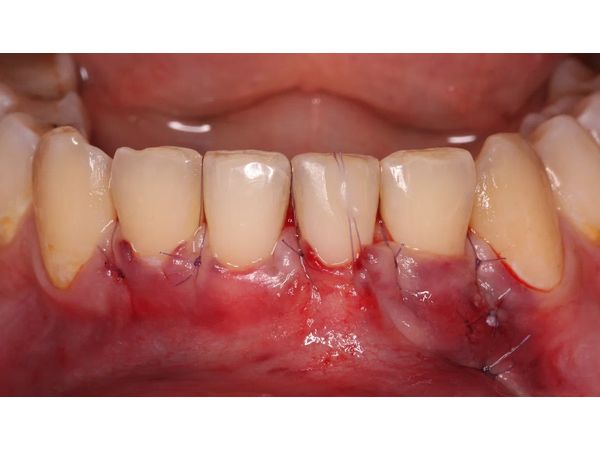

- Создали тоннельный доступ — подтянули сосочки вертикально к ретейнеру и добавили центральный композитный шов в области зуба с рецессией.

- Замерили необходимый объём тканей для трансплантации.

- Ввели трансплантат в тоннель и стабилизировали швами, которые прижимают и вытягивают лоскуты вдоль оси зубов.

В ходе операции участвовали все четыре резца, так как чем шире лоскут, тем лучше мобилизация. Также важно было равномерно утолщить десневой край, чтобы предотвратить рецидив.